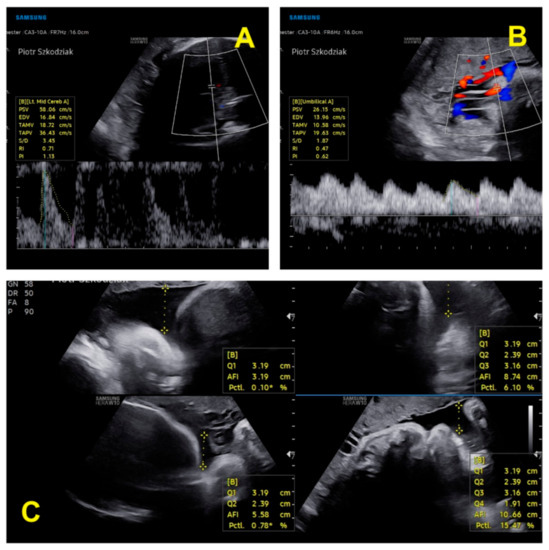

| Parameter | Twin 1 in Trimester II | Twin 2 in Trimester II | Twin 1 in Trimester III | Twin 2 in Trimester III |

|---|---|---|---|---|

| BPD (mm) (biparietal diameter) | 58.7–23w1d | 57–22w5d | 76.4–29w3d | 75.3–29w0d |

| HC (mm) (head circumference) | 221–24w1d | 207–22w6d | 275.3–29w3d | 261–27w6d |

| FL (femur length) (mm) | 40.8 mm–23w1d | 37.6–22w0 | 54.9–29w2d | 51.6–27w5 |

| AC (abdominal circumference) (mm) | 180 | 174 | 240 | 221.5 |

| AFI (amniotic fluid) | normal | normal | normal | normal |

| FHR/min (fetal heart rate) | 153 | 160 | 150 | 148 |

| EFW (g) (estimated fetal weight) | 570 | 493 | 1298 | 1057 |

| EFW discrepancy | 13.5% (assessment at 22 weeks 6 days) | 18.6% (assessment at 28 weeks 0 days) | ||